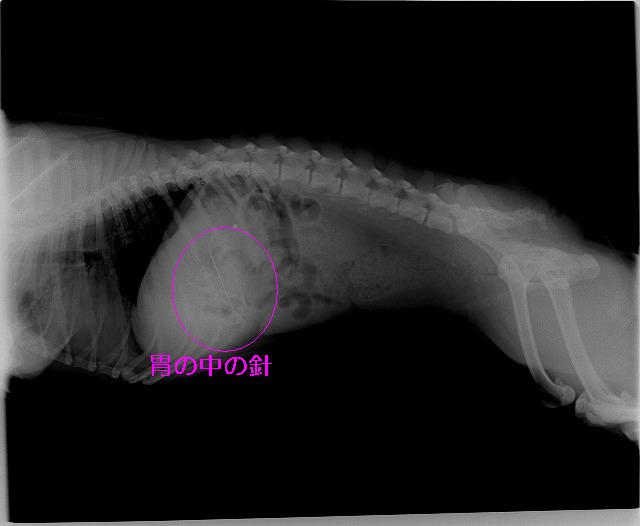

「ぬいぐるみを作っていたのですが、この時に使っていた針を飲み込んだかもしれません!」と言う事であるワンちゃんがいらっしゃいました。すぐにレントゲンを撮っておなかの中を調べてみると・・・

Img6576.jpg

Img6577.jpg

胃の中の針はすぐに見つけ出すことが出来ましたが、他にも何か胃の中にあるようです。